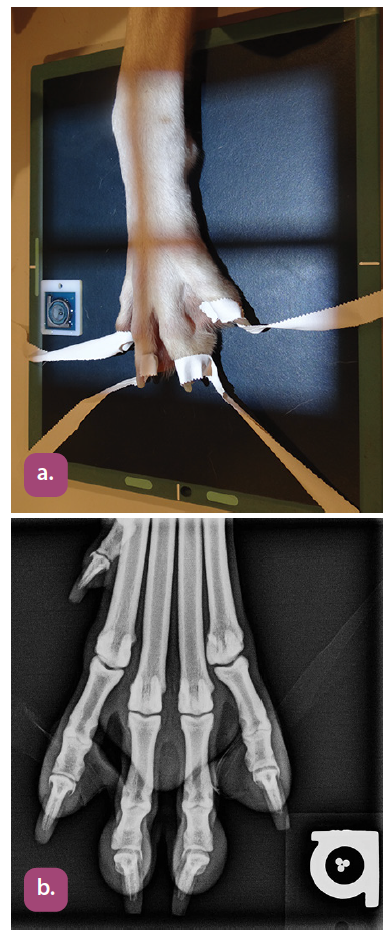

dorsopalmar projection of the digits

dorsopalmar projection of the metacarpus

dorsopalmar projection of the phalanges